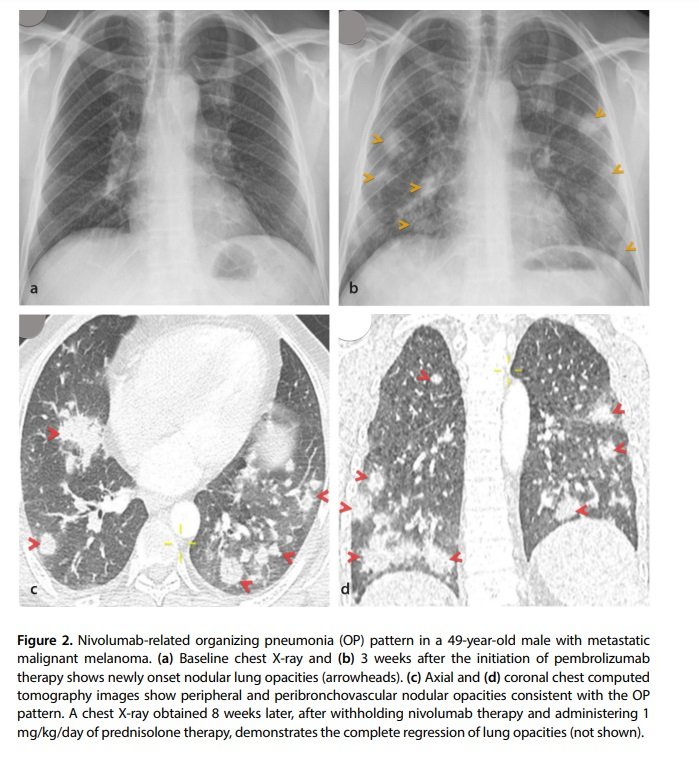

•The OP pattern is a form of acute lung injury and is the most common form of DILD